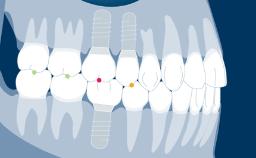

As próteses fixas implantossuportadas visam fornecer substitutos para dentes ausentes que são capazes de resistir à demandas funcionais e imitar com acurácia a estética das unidades denteais ausentes. Idealmente, a prótese deve ser indistinguível da dentição ao redor. Para atingir este objetivo, o clínico deve selecionar os melhores materiais disponíveis para enfrentar os desafios da situação clínica. Este módulo discutirá os materiais dentários disponíveis para a fabricação de próteses implantossuportadas e os princípios básicos envolvidos na seleção do material mais adequado para cada caso.